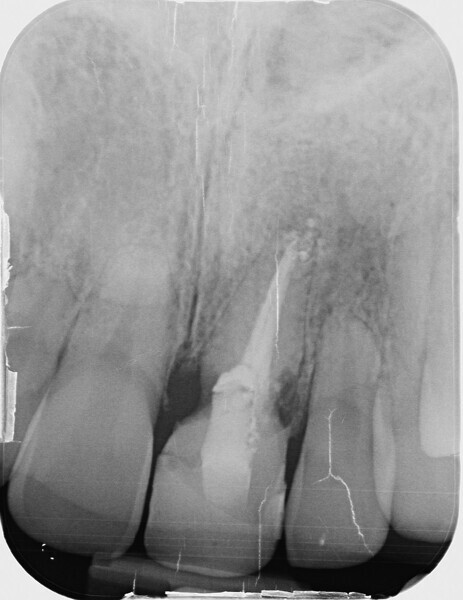

Fig. 2: Initial situation: tooth #21 exhibited marginal redness of the gingiva that bled when probed.